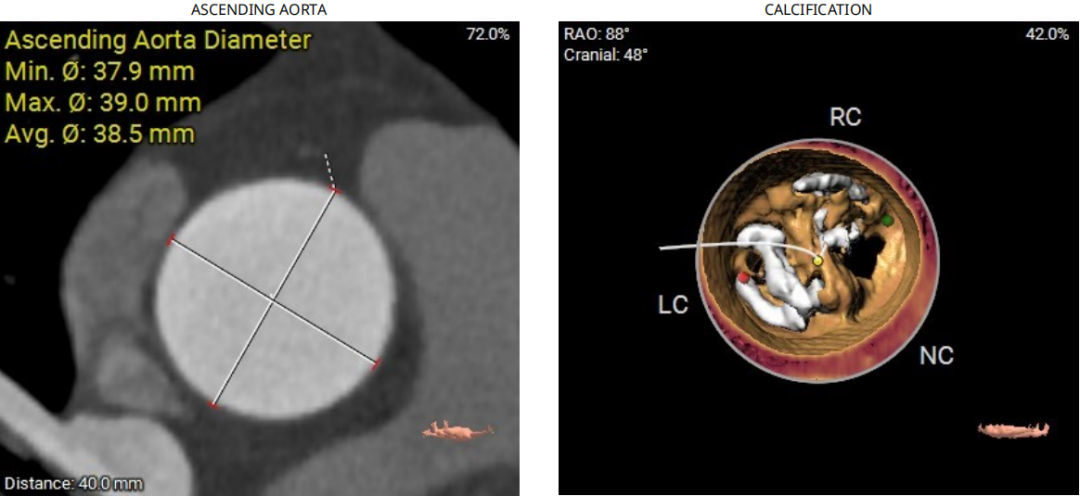

术前CT提示

主动脉瓣环折算直径22.0mm,LVOT直径20.7mm,瓣环及流出道平面可见钙化SOV 平均直径32.3mm,STJ直径30.0mm,升主动脉直径38.5mm;

左冠开口高度14.0mm;右冠开口高度15.8mm;

主动脉成角39°;

钙化评估: